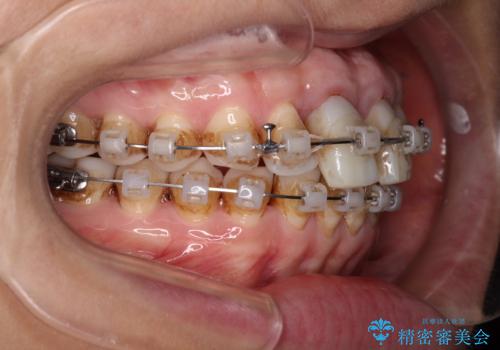

- 矯正装置

- クリアブラケット

- 治療期間

- 2年6ヶ月

- 治療回数

- 30回以上

初めは前歯のみの処置で改善を希望されていたため、広範囲に処置範囲を広げることで歯の幅がバランスする治療を提案しましたが、削らなければならない歯が増えてしまうため、患者様と相談して全顎矯正により前歯のスペースを閉じていくこととしました。

不適合なクラウンが装着されていたため、歯周ポケットが深くなっていましたので、矯正治療前に歯周外科処置を行って歯周ポケットを除去し、矯正治療後にオールセラミッククラウンにて補綴治療を行うこととしました。